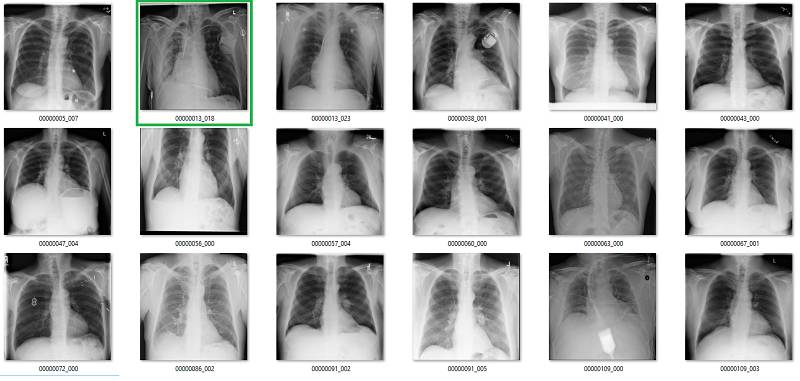

以下是模型的预测以及它们与数据集中的标注所做的比较:

真正类

绿色是真正类,其它的是错误的标签。

真负类

前 18 张有 1 到 2 个有争议,后面 18 张中红框都是错误的。

假正类

红色的都是错的,数据集中也出现了旋转和扭曲等异常情况(用红色问号标记)。

假负类

红色部分为严重错误标注。

尽管 AUC 是 0.7,但与标签错误率一致,我们的分类性能非常糟糕。该模型无法忽略错误的标签,输出合理的预测,它对标签噪声不具备鲁棒性。最重要的是,AUC 值没有反映诊断性能,这是一个很大的问题。

这一 AI 系统学习可靠地输出无意义的预测。它学习图像特征的方式使「opacity」的案例变得几乎没有模糊性,而「no opacity」的案例被判断为严重不正常的肺。